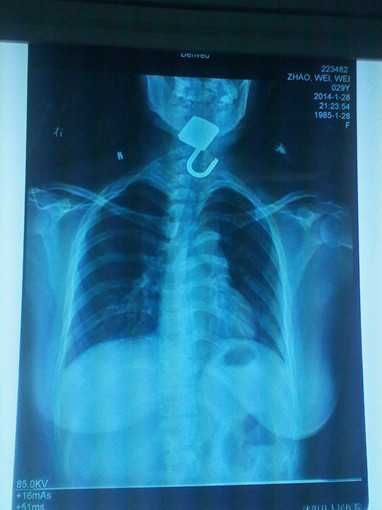

铁锁锁喉 生命垂危 巧手取出 化险为夷

1月28日,耳鼻喉科主任李强接诊一名吞食铁锁病人,因铁锁的锁勾勾在患者的食道入口处,该病人生命垂危。

该病人是一名精神病患者,在治病期间吞食铁锁,两天后才发现,急送城区一家医院。该院见是精神病人,铁锁又是勾在食道入口处,且食道入口处已经发炎,手术难受大且有风险。在推手不治的情况下,转来我院。

李强主任接诊查看后,及时与患者家人沟通后将病人推进手术室,在全麻情况下,历时一个多小时,终将铁锁取出,化险为夷。